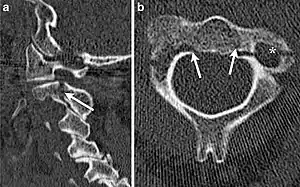

Hangman's fracture is the colloquial name given to a fracture of both pedicles, or partes interarticulares, of the axis vertebra (C2).[1]

| CT scan of hangman's fracture | |